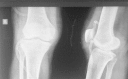

Methods: Eighteen subsequent cases of acute septic arthritis of hip and knee were included in this study. Complete hemogram, erythrocyte sedimentation rate (ESR), C-reactive protein (CRP), blood sugar, liver and kidney function test was done. Plain radiographs and ultrasound of affected joints were done. Joint aspirate was analyzed for gram staining, AFB staining, culture/sensitivity, biochemistry and cytology. Quantitative CRP was repeated every third day till normal CRP level was noted. Intravenous cloxacillin 25-50 mg/kg was started according to WHO protocol and was later changed to specific antibiotics after culture reports. Arthroscopic drainage and debridement of joints was done through standard portals and two tubes were placed in each joint for continuous suction and irrigation. Continuous suction irrigation was used till the effluent saline from the joint was clear. Functional outcome was documented as per Harris hip score for hips and Lysholm score for knee joint. Scoring was done before surgery, at one month and at three months. The duration of intravenous antibiotics and hospitalization was recorded.

Results: Out of eighteen cases 83.33% were males and 14.67% females. The mean age was 22 years (±12.01). The mean duration of symptoms was 4.33 days (±1.41). According to Gachter classification 88.88% of cases were stage 2 infection and 11.12% cases in stage 1 at the time of arthroscopy. The mean duration of hospital stay was 14.61 days (±4.01). Intravenous antibiotics were given for a mean period of 9.33 days (±2.16). The mean pre-operative Harris score was 13.6 (±2.07) which improved to 98 (±1.87) at 3 months and all the cases had painless normal range of movements. Mean pre-operative Lysholm score was 38.38 (±4.29) and it improved to 98.84 (±2.19) at 3 months. There were no sequelae of septic arthritis in any case.